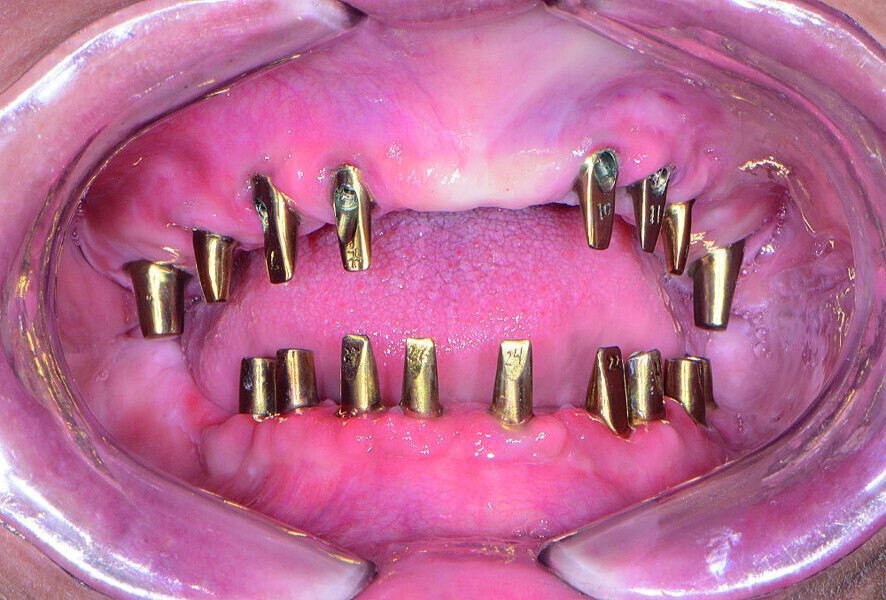

Fig 19 Piliers Inclusive fabriqués par CFAO